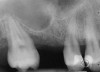

A 55-year-old male was referred for implant placement and prosthetic rehabilitation in the area of tooth No. 15. The tooth had been extracted 4 years prior. The radiograph revealed inadequate bone height for implant positioning (Figure 6). It was decided to insert an implant that was 11.5 mm in length and 3.75 mm in diameter, performing a slight osteotomic maxillary sinus lift. A heterologous bone graft also was planned to obtain a larger sinus lift.

A full-thickness mucoperiosteal flap was raised, and alternating osteotomes were used to prepare the implant site. After achieving a length of 7 mm (Figure 7A and Figure 7B), heterologous bone graft was implanted and the osteotome sequence was repeated. The implant showed primary stability.

Second-stage surgery was performed after 4 months (Figure 8); healing abutments were placed and the soft tissue was allowed to heal for 5 more weeks. Then, splinted porcelain-fused-metal (PFM) crowns supported by custom gold abutments were delivered (Figure 9 and Figure 10).

Figure 6  Preoperative radiograph of the area around tooth No. 15.

Figure 8  At 4 months after treatment, the radiograph revealed the presence of a bone layer surrounding the implant.

Figure 10  Posttreatment radiograph, after cementation of the final restorations.

Figure 10